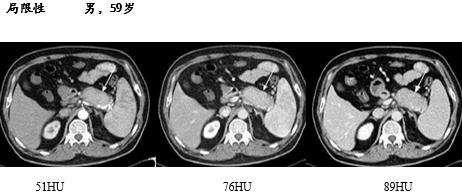

局限性

动态增强 CT 是鉴别胰腺癌和局限性 AIP 的重要手段。

AIP 的低密度肿块在增强早期密度低于周围正常胰腺组织,延迟期则密度均匀一致;而胰腺癌表现为不规则的低密度乏血供肿块,肿瘤远端胰腺萎缩、胰管扩张及周围血管受累。